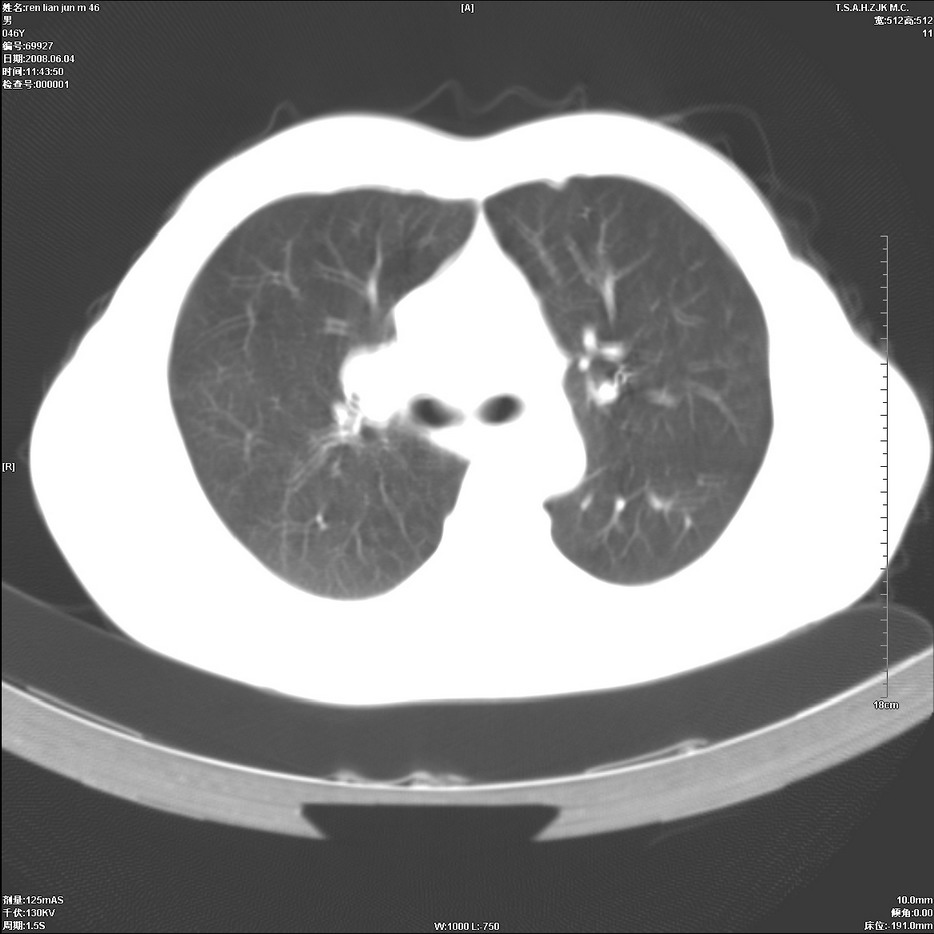

以下是引用qiu999在2008-6-5 17:14:00的发言:[br]考虑右肺中心型肺癌.颅内应做增强检查.

以下是引用形影不离在2008-6-5 19:18:00的发言:[br]右肺中心型肺癌并纵隔及左侧腋窝淋巴结转移,颅内应做增强检查。

以下是引用杀毒软件在2008-6-5 18:33:00的发言:[br]支持考虑右肺中心型肺癌,颅内病变是不是转移,不好说